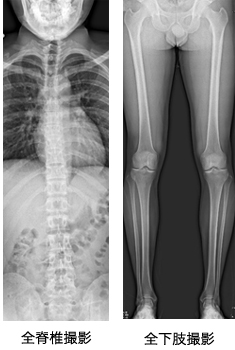

スロット撮影とは、X線をスリット上に絞り、映像系を平行移動させながら画像を収集し、得られた画像をつなぎ合わせて1枚の長尺画像に再構成しています。

また、スリット上にする事で散乱線の影響を抑えた高画質な画像が低線量で撮影出来ますので、患者様の被爆低減にも繋がっています。当院では、この撮影法で全脊椎と全下肢を撮影しています。